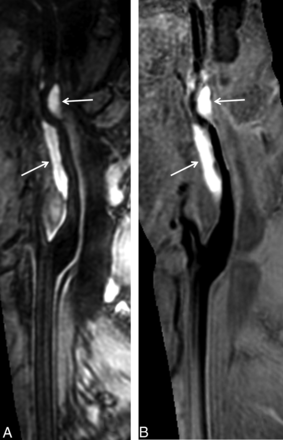

In measuring luminal stenosis of diseased arteries, the Cohen κ value between 3D TOF MRA and SNAP imaging was 0.82 (P < .001). Figure 1 demonstrates mild stenosis in the basilar artery on the MRA image derived from SNAP imaging (Fig 1A), corresponding to the TOF MRA image (Fig 1B), while the hyperintense signal on the SNAP vessel wall image (Fig 1C) indicates IMH. One patient with mild stenosis on 3D TOF MRA was classified as having moderate stenosis by SNAP imaging, and 2 patients with severe stenosis on 3D TOF MRA were diagnosed as having occlusion. All IMHs on multisequence imaging were successfully identified by SNAP imaging. IMH appeared hyperintense on the 3D SNAP image, corresponding to the 3D MERGE images (Fig 2). In addition, the characteristics of pseudoaneurysm, intimal flaps, and double lumen on multisequence imaging were also accurately determined by SNAP imaging (Fig 3). Figure 4 is an example of the excellent joint visualization of luminal changes and IMH in the vessel wall on SNAP images after color-coded reconstruction.

SNAP imaging depicts intramural hematoma. The intramural hematoma in the internal carotid artery appears hyperintense on both 3D MERGE (A, white arrows) and SNAP images (B, white arrows).

All the IMHs of this study population were successfully detected by 3D SNAP imaging. The IMH exhibited hyperintense signals on SNAP images, indicating the component with a short T1. It has been shown that the SNAP imaging sequence increased the contrast between hemorrhage and the vessel wall by another 35%, which allows more detection of carotid intraplaque hemorrhage compared with the widely used 3D magnetization prepared rapid acquisition of gradient echo sequence.14 In previous studies, the IMH was evaluated by 2D T1-weighted MR imaging with fat saturation.11⇓–13 However, acquisition of 2D T1-weighted images is time-consuming and has limited longitudinal coverage. Recently, the 3D black-blood T1-weighted imaging technique has been used to detect IMH in patients with arterial dissection.19⇓–21 Taking advantage of large coverage, black-blood effect, and high spatial resolution, 3D black-blood imaging sequences seem to be a substitute for 2D imaging techniques. Similar to the 3D T1-weighted imaging sequences, 3D SNAP imaging techniques enable fast and high-resolution imaging with large longitudinal coverage of up to 250 mm. Benefiting from the large coverage of SNAP imaging, the extent of IMHs, particularly those involving multiple vascular beds, can be delineated.